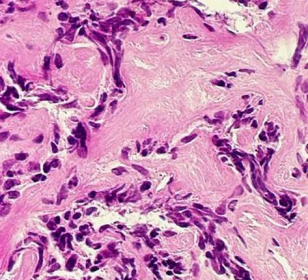

<p> Coordonné par Bertrand Nadel, Directeur du Carnot CALYM, directeur de Recherche Inserm et directeur de l’équipe « Instabilité génomique et hémopathies humaines » du Centre d’Immunologie de Marseille-Luminy (CIML, Inserm/AMU/CNRS), le projet ATLAS réunit les équipes scientifiques du CIML (dont l’équipe de P. Milpied), du Carnot CALYM (dont l’équipe de B. Nadel / S. Roulland est membre).</p> <p> ATLAS a pour ambition de fournir une première analyse dynamique à haute résolution de lymphomes folliculaire et diffus à grandes cellules B, dans leur microenvironnement immunitaire. En décryptant, via des techniques d’analyse en cellules uniques, les bases de la physiopathologie de ces cancers, les équipes de recherche vont construire pour chacun d’eux un « Atlas » single-cell RNA-seq sur un grand nombre de patients, afin d’identifier les paramètres biologiques clés associés à la transformation, la croissance tumorale, la rechute et la résistance au traitement.</p> <p> Le projet ATLAS bénéficiera d’échantillons biologiques issus de la collection CeVi de cellules vivantes de lymphomes, mise en place par CALYM, et conditionnés pour l'analyse scRNA-Seq.</p>